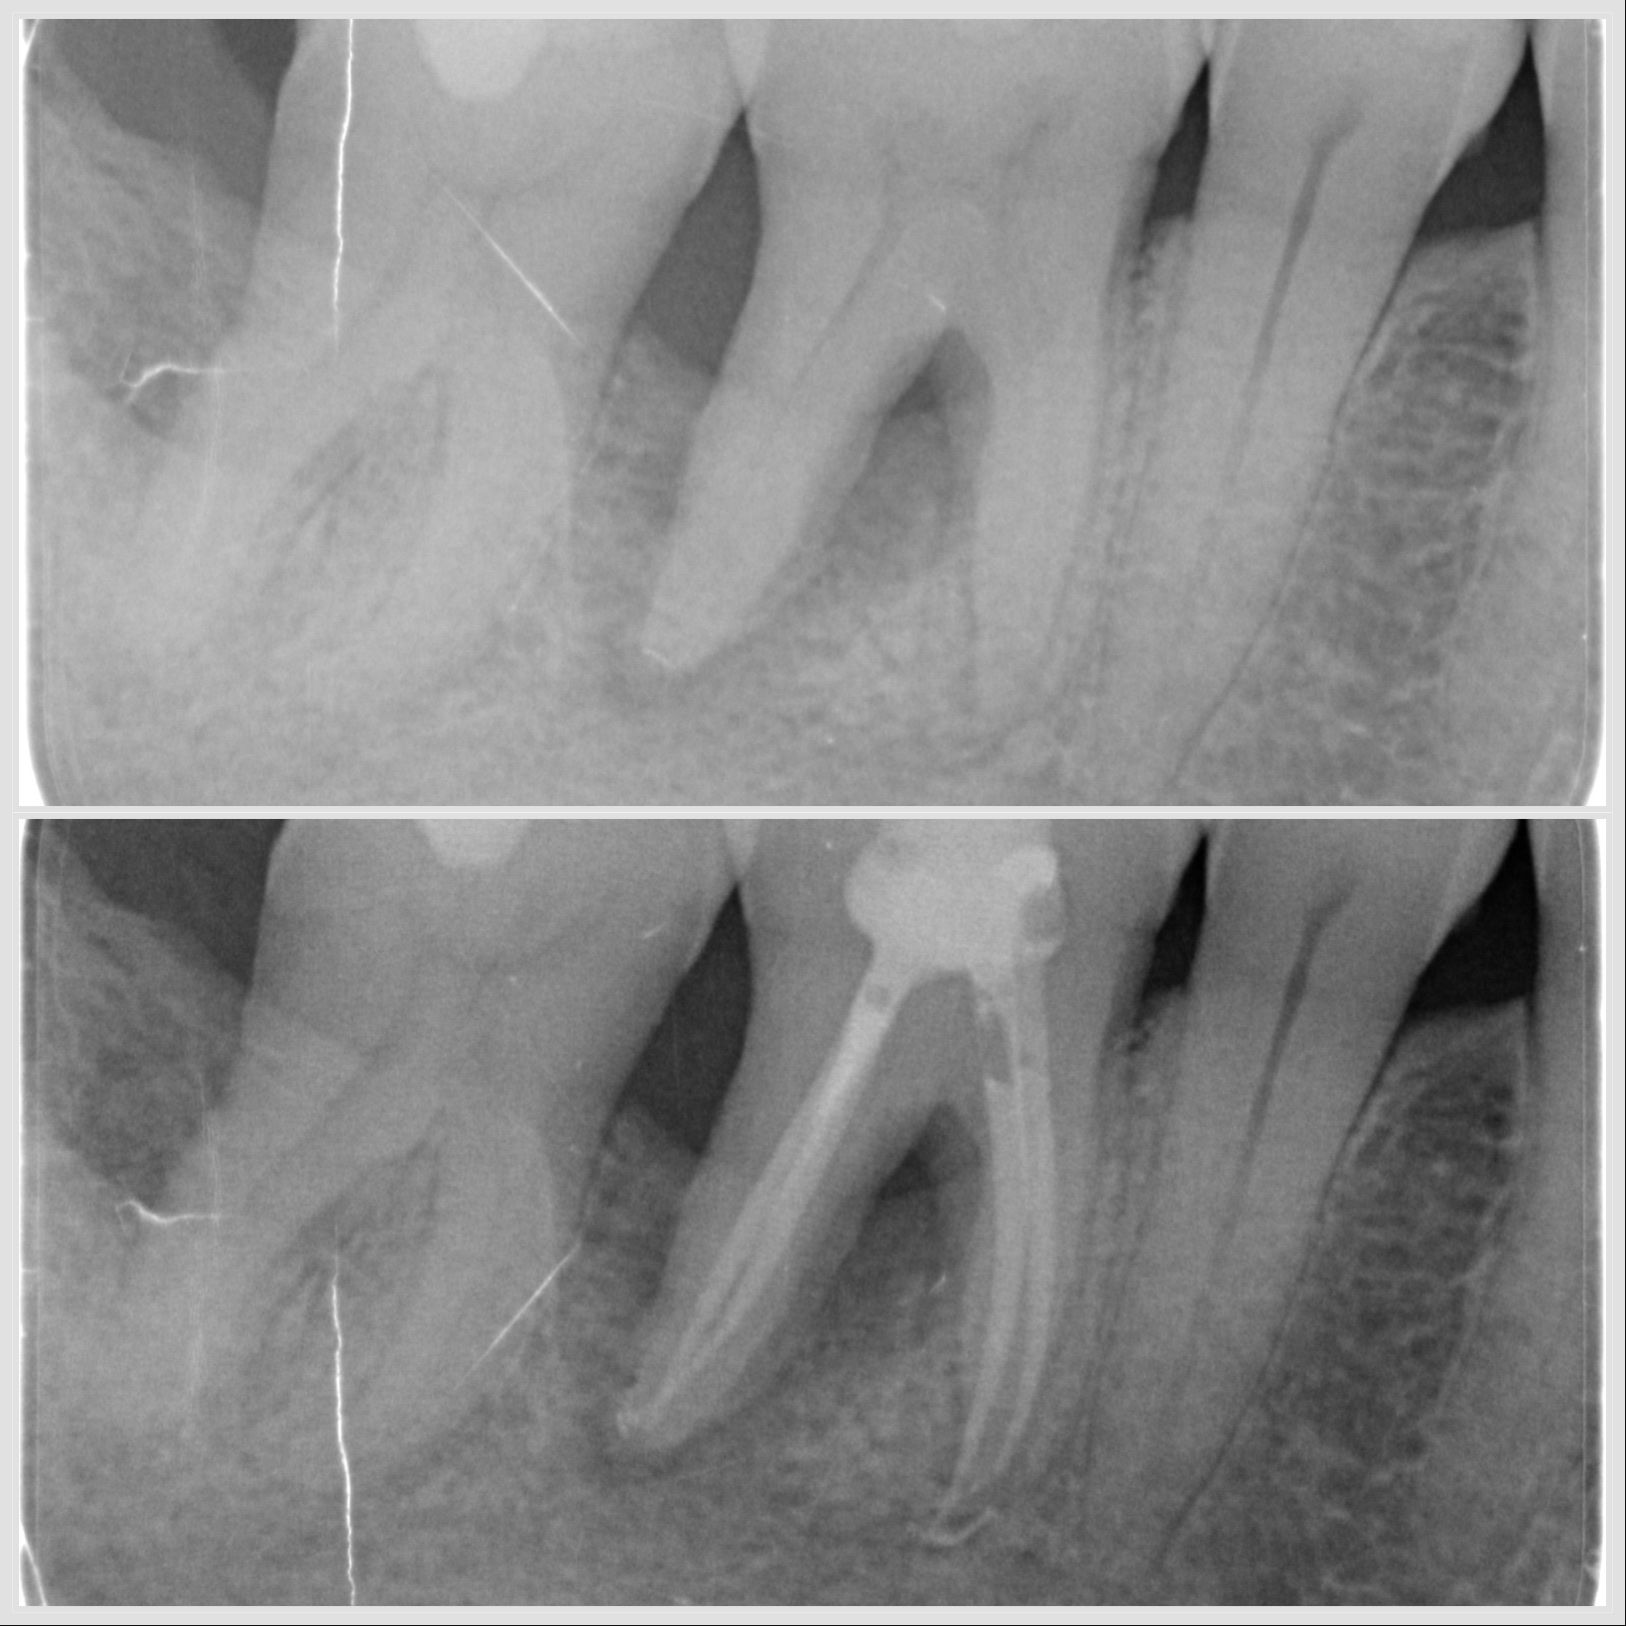

Lésion endo-parodontale sur molaire mandibulaire traitée en endodontie et parodontologie à Apolline Dental Care à Corbeil-Essonnes

Lésion endo-parodontale

Traitement endodontique sur prémolaire avec trois canaux réalisé à Apolline Dental Care à Corbeil-Essonnes

Endodontie sur prémolaire à 3 canaux